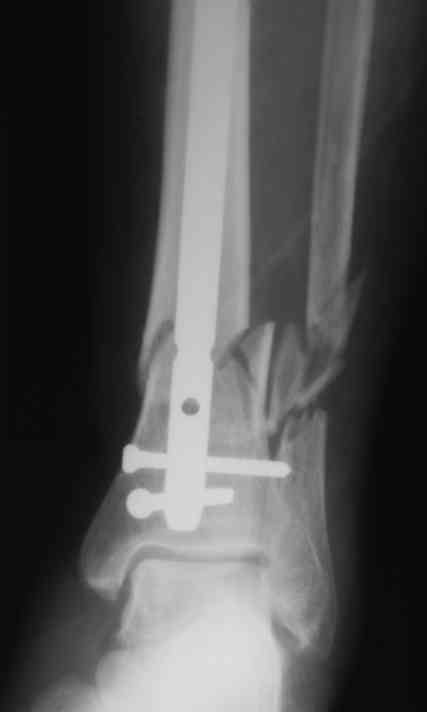

Уважаемые коллеги!БИОС занимаемся недавно. Хотелось бы услышать Ваше мнение па данному

клиническому примеру. Пациенту 74 года. Выполнен открытый БИОС, обнаружен выраженный

остеопороз, один из проксимальных винтов(самый верхний) и один из дистальных (нижний)

"сорвались". В средней трети - косо-поперечный перелом (на фото не захвачен) с хорошей

репозицией. Клинически фиксация переломов стабильна. Выполнить МОС малоберцовой кости не

представлялось возможным из-за фликтен по латеральной поверхности голени. Вопросы:-

необходимость дополнительной внешней иммобилизации;- сроки динамизации БИОС